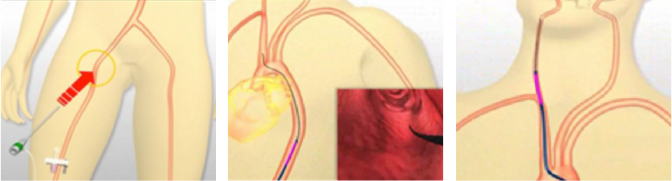

02脳血管内手術(カテーテル手術:脳動脈瘤コイル塞栓術)

極小のプラチナコイルがマイクロカテーテルを経由して脳動脈瘤に導かれます。コイルは柔軟性に富むため、脳動脈瘤の形状に沿って留置されます。 脳動脈瘤はコイルで充填されて、脳動脈瘤内部への血流を防ぎます。